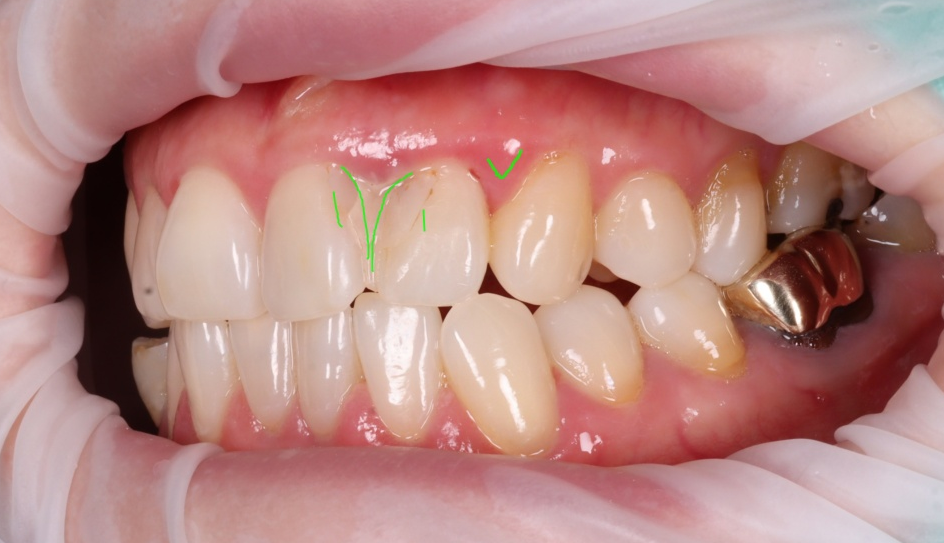

이번에 내원하신 환자분은 50대 여성으로, 불과 12일 전에 다른 치과에서 앞니 레진 치료를 받으셨다고 해요.

그런데 거울을 볼 때마다 색상이 너무 이질적이고 뭔가 내 치아 같지 않고 치료한 티가 나서 도저히 웃을 수가 없다는 고민으로 찾아오셨죠.

하지만 정밀 검진을 통해 발견한 진짜 문제는 단순히 심미적인 부분만이 아니었습니다.

촬영일 : 251230

앞니 사이 공간을 레진으로

꽉 메워둔 상태였어요.

치아 사이는 반드시 치실이 매끄럽게 통과할 수 있는 미세한 틈이 있어야 음식물 찌꺼기가 빠지고 잇몸이 건강하게 유지돼요.

그런데 이걸 꽉 막아버리니 그 안에서 세균이 번식하며 이미 뼈(치조골)가 흡수되는 치주염이 진행되고 있었죠.

엑스레이에서 현재 환자분 뼈 상태를 그려봤는데요.

앞니 쪽에서 뼈 흡수가 많이 되어 라인이 위로 올라가는 것을 볼 수 있었고, 만져봤을 때 경미한 흔들림도 있었죠..

환자분께 현재 상태의 심각성을 말씀드렸어요.

"지금은 색이랑 형태보다 잇몸 뼈가 흡수되는 게 더 문제입니다. 레진이 분리가 되어서 사이가 닦여야 하는데 붙어있어 관리가 되지 않는 형태예요."라고요.